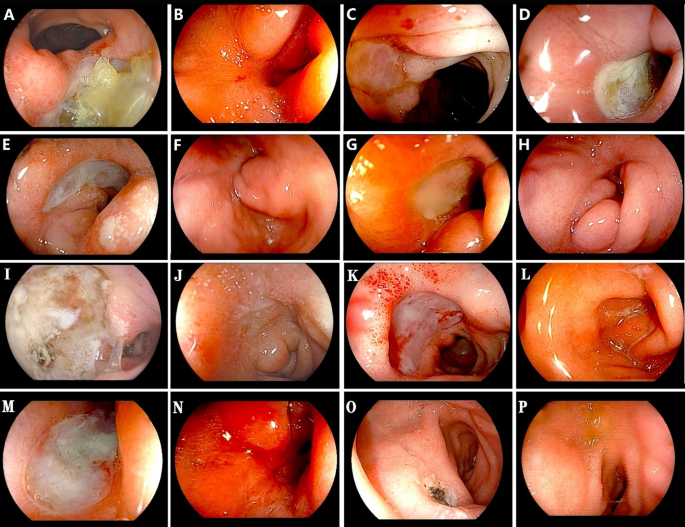

Endoscopic findings of patients in the REDU cohort are summarized in Table 3; Fig. 1. Among the 30 REDU patients, 13 (43.3%) had ulcers located in the postbulbar duodenum, 12 (40.0%) in the anterior wall of the duodenal bulb, and 5 (16.7%) in the greater curvature of the duodenal bulb; three of these patients had “kissing ulcers”.

Endoscopic images of DBU and description of treatment outcomes. (A) Image of the duodenal bulb ulcer (DBU) caused by prior HP infection in Case 2 of Group A; (B) Healing of DBU after HP eradication; (C,D) Recurrence of DBU following omeprazole dose reduction. (E) Image of the 3rd DBU recurrence in Group A Case 3 after omeprazole dose reduction; (F) Healing of DBU after 40 mg omeprazole treatment; (G) Recurrence of DBU after omeprazole dose reduction; (H) Healing of DBU under maintenance therapy with low-dose omeprazole combined with azathioprine; (I) Image of DBU caused by prior HP infection in Case 10 of Group A; (J) Scar formation after omeprazole administration; (K) Recurrence of DBU after omeprazole dose reduction; L. Healing of DBU under maintenance therapy with low-dose omeprazole combined with azathioprine; M-N. Image of the DBU in Group B and healing after treatment. O-P: Image of the DBU in Group C and healing after HP eradication.

Eosinophilic DBU (in both Groups A and B) were characterized by large, shallow, pan-like lesions covered with a clean, thin white exudate (Fig. 1C, D, E, G, K and M)—distinct from the prior HP-associated DBU cases in Group A (Fig. 1A and I) and Group C(Fig. 1O), both of which typically featured a dirty ulcer base .

Regarding giant DBU, 17 patients (89.5%) in Group A and 6 patients (54.5%) in Group B had this finding, with a statistically significant difference between the two groups (P < 0.001). Twenty-eight patients (93.3% of the REDU cohort) underwent colonoscopy, which revealed terminal ileitis in 13 cases (46.4% of colonoscopy recipients) and proctocolitis in 8 cases (28.6%). Fourteen patients (46.7% of the REDU cohort) underwent capsule endoscopy, with findings including enteritis (6 cases, 42.9% of capsule endoscopy recipients), duodenal ulcer (2 cases, 14.3%), normal findings (4 cases, 28.6%), and capsule impaction secondary to duodenal bulb stenosis (2 cases, 14.3%).

All patients in the REDU cohort underwent repeated gastroscopy due to persistent abdominal pain or for ulcer surveillance. Follow-up gastroscopy revealed that 21 patients (70.0%) had persistent DBU, 13 patients (43.3%) had duodenal bulb stenosis (9 cases in Group A), and 4 patients (13.3%) had duodenal mucosal erosion. Pathologically, pre-treatment duodenal bulb biopsies from the REDU cohort showed EOS counts of ≥ 100 cells/HPF in 17 patients (56.7%) and ≥ 50 cells/HPF in 13 patients (43.3%). Gastric antrum biopsies revealed EOS counts of ≥ 100 cells/HPF in 3 patients (10.0%) and ≥ 30 cells/HPF in 8 patients (26.7%). No statistically significant difference in EOS counts per HPF was observed between Group A and Group B, either in the duodenal bulb (P = 0.16) or in the gastric antrum (P = 0.70).

Interestingly, we observed striking phenotypic differences between HP-associated ulcers and eosinophilic post-eradication ulcers—differences that have clinical implications for diagnosis. Eosinophilic post-eradication ulcers differ from HP-associated ulcers in three key ways: (1) clean vs. dirty ulcer base17. (2) shallow, pan-shaped vs. deep, irregular lesions; (3) less surrounding mucosal edema18. Histopathologically, HP-associated peptic ulcers are characterized by a marked neutrophilic infiltrate, with concurrent eosinophilic infiltration observed in some cases. In contrast, REDU or EGIDs are pathologically defined by an eosinophil-predominant inflammatory infiltrate, in which neutrophilic involvement is minimal or even absent. Capsule endoscopy is limited here due to stenosis-related capsule impaction and inability to obtain biopsies, reinforcing upper gastrointestinal endoscopy with biopsy as the gold standard for diagnosis.